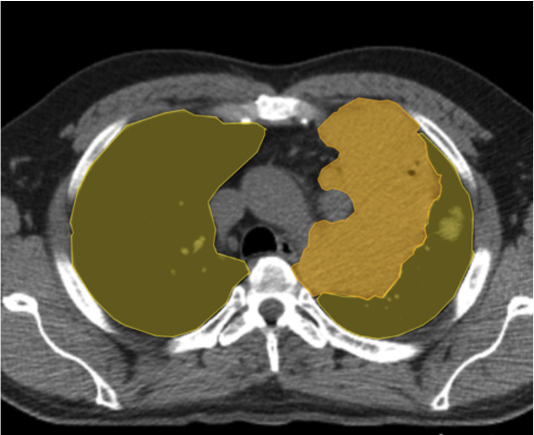

- CNNs (Convolutional Neural Networks) and U-Net are widely adopted for identifying structures, segmenting organs, and detecting anomalies with minimal error.

- High-quality annotated data fuels accurate AI models, allowing researchers to train algorithms effectively for multiple imaging modalities like MRI, CT, and PET.

- Advanced AI converts 2D scans into detailed 3D models, assisting surgeons in pre-operative planning and precision medicine.

AI-powered imaging detects tumours at early stages, helping oncologists create patient-specific treatment plans.